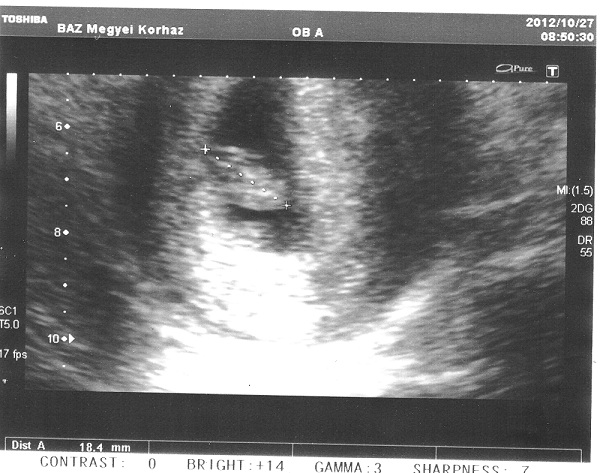

A mai eredmény:) : Kép 8 hetes UH

Minden ok, 18 mm, pulzus 140/perc, a korának éppen megfelelő méretű legényke/leányka :)

Nagyon boldogok vagyunk! Mindenkinek hasonlókat kívánunk!